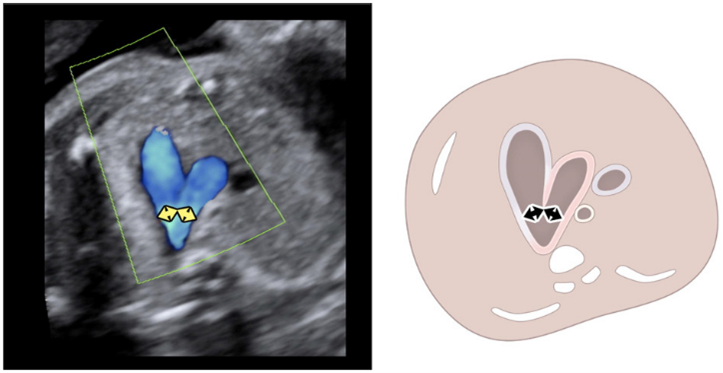

Fetoly is the first real-time AI solution for fetal ultrasound, helping to ensure a complete and standardized examination. Integrating with most ultrasound systems, it provides instant feedback to help diagnostic confidence and help improve pregnancy outcomes.

• Real-time ratios supporting the detection of pathologies